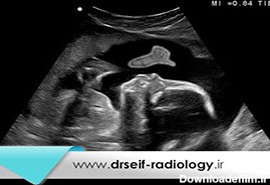

عکس جنین مرده شیش هفته

مرده زایی همان مرگ جنین در رحم، پس از هفته بیست بارداری می باشد. مرده زایی و سقط جنین هر دو سبب مرگ جنین می شوند اما سقط جنین شامل مرگ جنین قبل از هفته بیست بارداری می باشد.